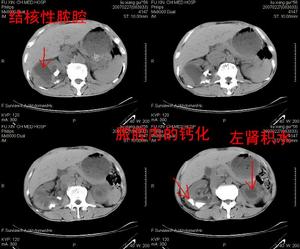

腎結核對側腎積水是腎結核的晚期併發症,由膀胱結核引起。根據中國資料的統計1959年在1,334例腎結核病例中繼發對側腎積水者占16%。1962年在4,748例腎結核病例中繼發對側腎積水者占13.4%。

腎結核對側腎積水(2)輸尿管下段狹窄:對側輸尿管口附近的結核病變可經黏膜表面直接蔓延或黏膜下層的浸潤,使輸尿管口以上的一段輸尿管亦因疤痕形成而發生狹窄,引起對側腎和輸尿管積水。

(3)輸尿管口閉合不全:正常輸尿管由於在膀胱壁中的有斜行的壁間段所具有括約肌的作用,在膀胱收縮時可阻止尿液回流至尿管和腎盂。輸尿管口周圍的結核病變可由於纖維化使管僵硬而失去括約肌作用,導致輸尿管口閉合不全。因此,膀胱內尿液經常可逆流到對側尿管和腎盂內,引起腎和輸尿管積水。

(4)膀胱攣縮:嚴重的膀胱結核最後必然造成膀胱攣縮。膀胱攣縮使膀胱失去在充盈過程中逐漸擴大容量而維持正常膀胱壓力的能力,造成膀胱內壓力很高,特別在膀胱有炎症時,經常刺激膀胱收縮,使壓力更高。膀胱內的長期高壓狀態可阻礙腎盂和輸尿管的尿液引流或造成膀胱尿逆流至輸尿管和腎盂,引起對側腎和輸尿管積水。

以上四種病變往往是合併存在的。腎結核繼發對側腎積水主要是由於輸尿管下端的機械性梗阻,尿液逆流,和膀胱高壓三個因素所造成。腎積水嚴重時可導致腎實質萎縮,腎功能減退,亦較易發生繼發感染。